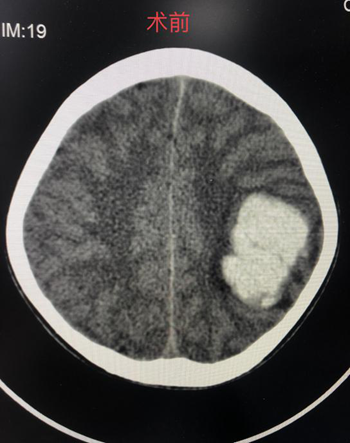

(术前脑部CT)                       (术后脑部CT)

近日,廖驭国团队成功抢救一名动静脉畸形破裂出血的14岁儿童。该患者经外院紧急转送至我院,入院时神志嗜睡,外院CT提示左侧颞顶叶急性脑出血。神经外科首诊医生廖军研判,患者高度疑似颅内动静脉畸形破裂出血,“时间就是大脑”情况十分紧急,急需手术治疗,马上汇报神经外科主任、神经介入中心主任廖驭国同时向家属解释病情并经得同意后,在麻醉科医生精准麻醉和严密检测下,廖驭国带领神经外科李海堃副主任医师为患者进行颅内动静脉畸形栓塞术,术中完美栓塞畸形团,顺利完成手术。